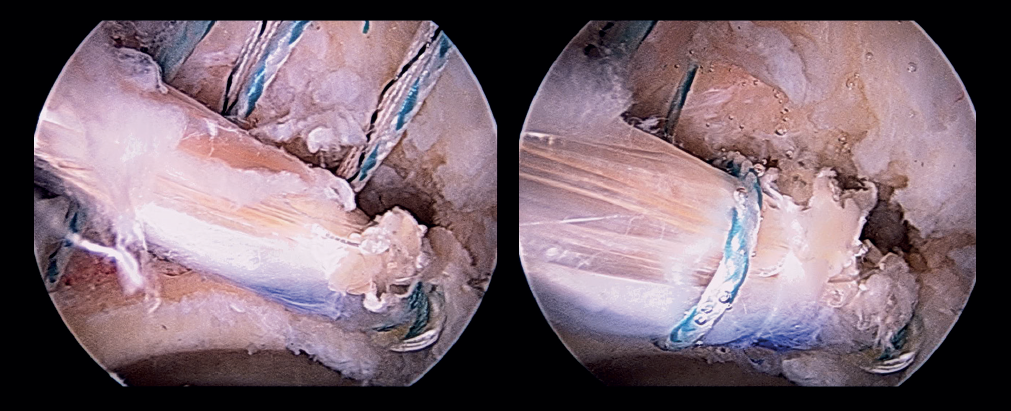

Capsular reconstruction procedure

Treatment of the capsule defect is carried out through capsular reconstruction using the modified kite technique described by Ellman(8). To perform this technique, we measure the dimensions of the proximal-distal capsule defect using the shoulder capsular reconstruction guide (Arthrex). It is important to measure the capsule defect in extension in order to avoid discordances. The last step in the preparation phase is to place two distal simple sutures in the native capsule using a SlingShot® (Stryker) suture passing device, and which will serve as a guide for the definitive sutures (Figure 8). The distal anterior suture is passed and reserved through the accessory DALA, and the distal posterior suture is passed and reserved through the DALA. Lastly, we prepare and cut an acellular dermal graft (Epiflex®) suited to the dimensions of the graft (in this case 2 x 2 cm). One of the extremities of the sutures of the anchorings previously placed at acetabular level and reserved in the proximal middle anterior portal (PMA) is extracted through the DALA and is passed through the proximal portion of the graft using Scorpion® (Arthrex) forceps. In the distal portion of the graft we also introduce FiberWire® number 2 sutures using Scorpion® forceps (Figure 9). Once the graft has been prepared, it is placed inside the joint and fixed at proximal level (Figure 10). Fixation of the distal portion of the capsule is then carried out. The point of this distal fixation is a soft tissue-to-soft tissue anastomosis in the zona orbicularis, which often marks the distal extent of the capsule defect according to most of the capsulectomy procedures. For this purpose we use the stitches previously placed and reserved in the accessory DALA and the DALA as a shuttle. Medial and lateral fixation to the capsule remains is then performed with FiberWire® number 2 stitches (Figure 11). The sutures are knotted with the hip in 10º flexion and neutral rotation. Finally, we check the stability of the graft through flexion and rotation movements. An illustration of the final result of the capsular reconstruction procedure and of the segmental labral reconstruction is shown (Figure 12).